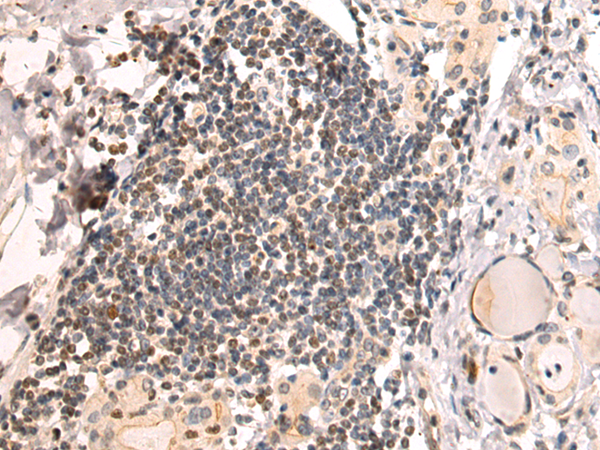

分类: 科研抗体货号: P11293别名: DLEC, HECL, BDCA2, CD303, CLECSF7, CLECSF11, PRO34150应用: IHC反应种属: Human